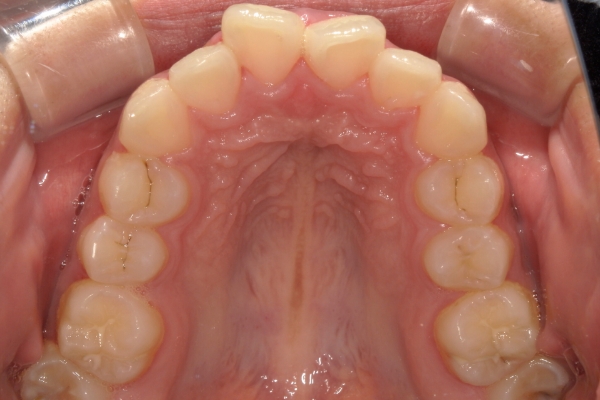

BEFORE

治療前

AFTER

治療後

上顎前歯が1 cm近く前方に出ており、叢生を改善しつつ前歯を大きく引っ込めるために上下顎小臼歯の抜歯が必要と診断しました。治療では奥歯の噛み合わせのズレも整え、治療後は前歯でも奥歯でも食べ物が噛みやすくなったと、患者さまに非常に満足していただけました。